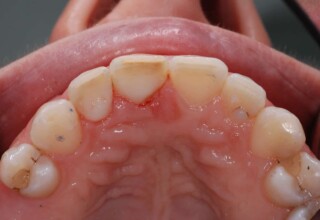

Composite Resin Veneers

Resin veneers are an inexpensive mode of esthetic improvement of anterior teeth, premolars also. Their potential is admirable and their limit is the operator’s clinical dexterity and imagination. In this case there were multiple problems with the upper four incisors: staining, poor inclinations, diastemas, multishading, poor interrelationship and poor tooth-gingiva ratios. They were restored with four direct composite resin veneers (one on a porcelain implant crown!) which were manufactured intraorally!!!